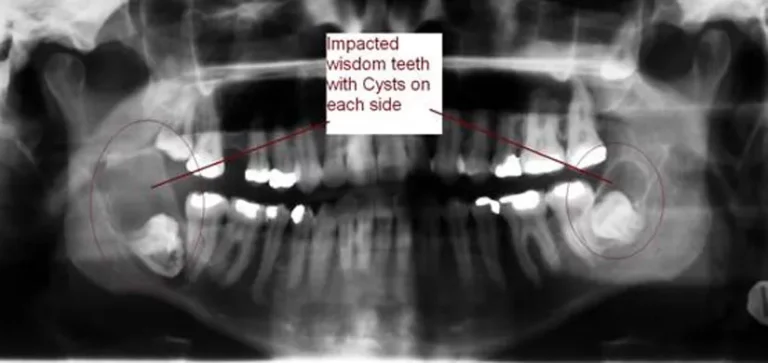

In some cases, the sac surrounding exposed bone of an impacted wisdom teeth or wisdom teeth extraction or tooth can develop fluid-filled cysts or, rarely, tumors. These can cause damage to the surrounding bone of impacted wisdom teeth and neighboring teeth if left untreated.

Pre-Operative Xray Required

OPG

CBCT